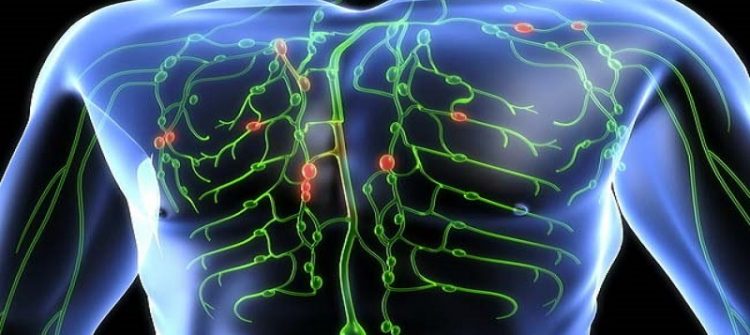

Dünya çapında yaklaşık olarak 250 milyon kişiyi etkileyen lenfödem, kronik ve ilerleyici bir hastalık. Yüz, genital, kol, bacak gibi vücudun…

Fizik tedavi ve rehabilitasyon programları, özel egzersizler, manuel terapi, sıcak-soğuk tedaviler, elektroterapi ve diğer modaliteleri içerebilir. Bu tedavi yaklaşımları, kas ve eklem fonksiyonlarını geri kazandırmak, ağrıyı azaltmak, dolaşımı iyileştirmek ve hastaların günlük yaşamlarına geri dönmelerine yardımcı olmak için kullanılır.